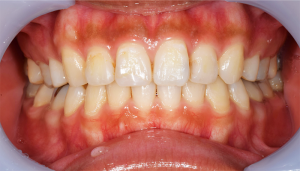

歯石除去

治療前

治療後

| 年齢 | 25歳・男性 |

| 主訴 | 歯石をとりたい・検診 |

| 治療内容 | 各種検査・歯石除去 |

| 治療期間 | 60分 |

| 費用 | 初診料3,000〜4,000円前後 +歯石除去約1,000円 |

| リスク・副作用 | ・処置後に歯がしみることがあります。 ・歯と歯の間に隙間ができるので、息が漏れ発音しにくいと感じることがあります。 ・歯ぐきの炎症が軽減すると歯ぐきが引き締まり、歯が長く見えることがあります。 |

| 担当者所見 | 前歯の裏側にすぐに歯石が溜まってしまいザラザラして気になるとご相談いただいたので適切な歯ブラシの当て方とフロスの通し方をお伝えさせて頂きました。 |